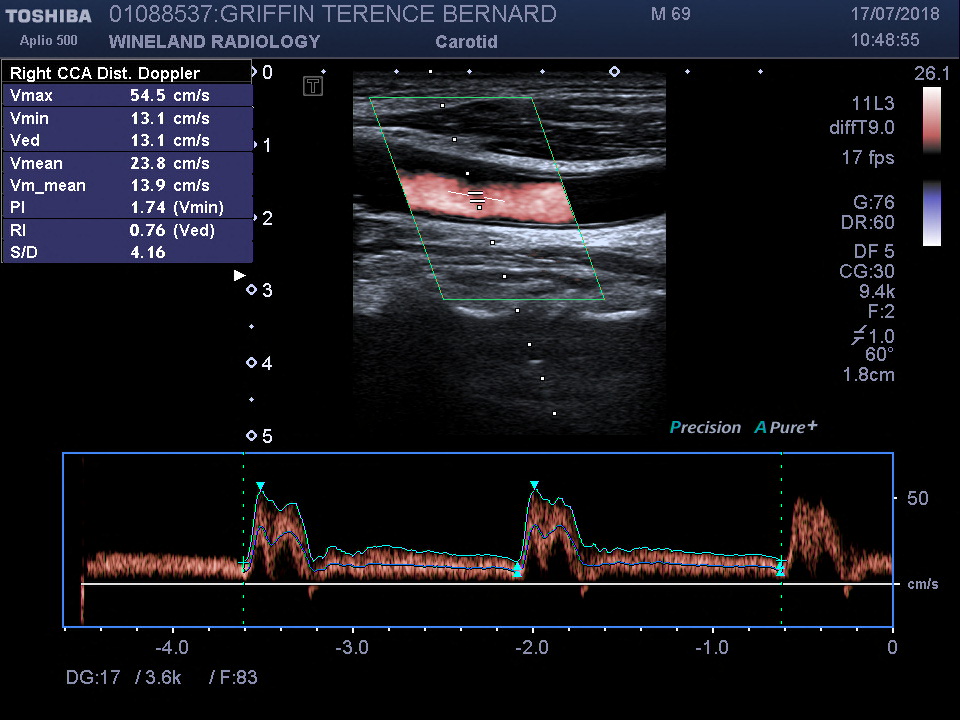

leg top

Ultrasound image of my carotid artery.

Meanwhile, my neurologist was still concerned about the cause of my accident and ordered a further series of tests: MRI's of my brain and brain stem, and x-rays and a ultrasound of my neck. The MRI indicated that I had had at least three minor strokes, the last and most serious of which had caused the accident. The stroke was caused by the cut-off of blood coming through the artery at the back of my neck (through the spine), which in turn was caused by arthritis in my spine. The ultrasound indicated that my carotid arteries were fine. In one sense the results were positive: the stroke was not caused by blood clots.